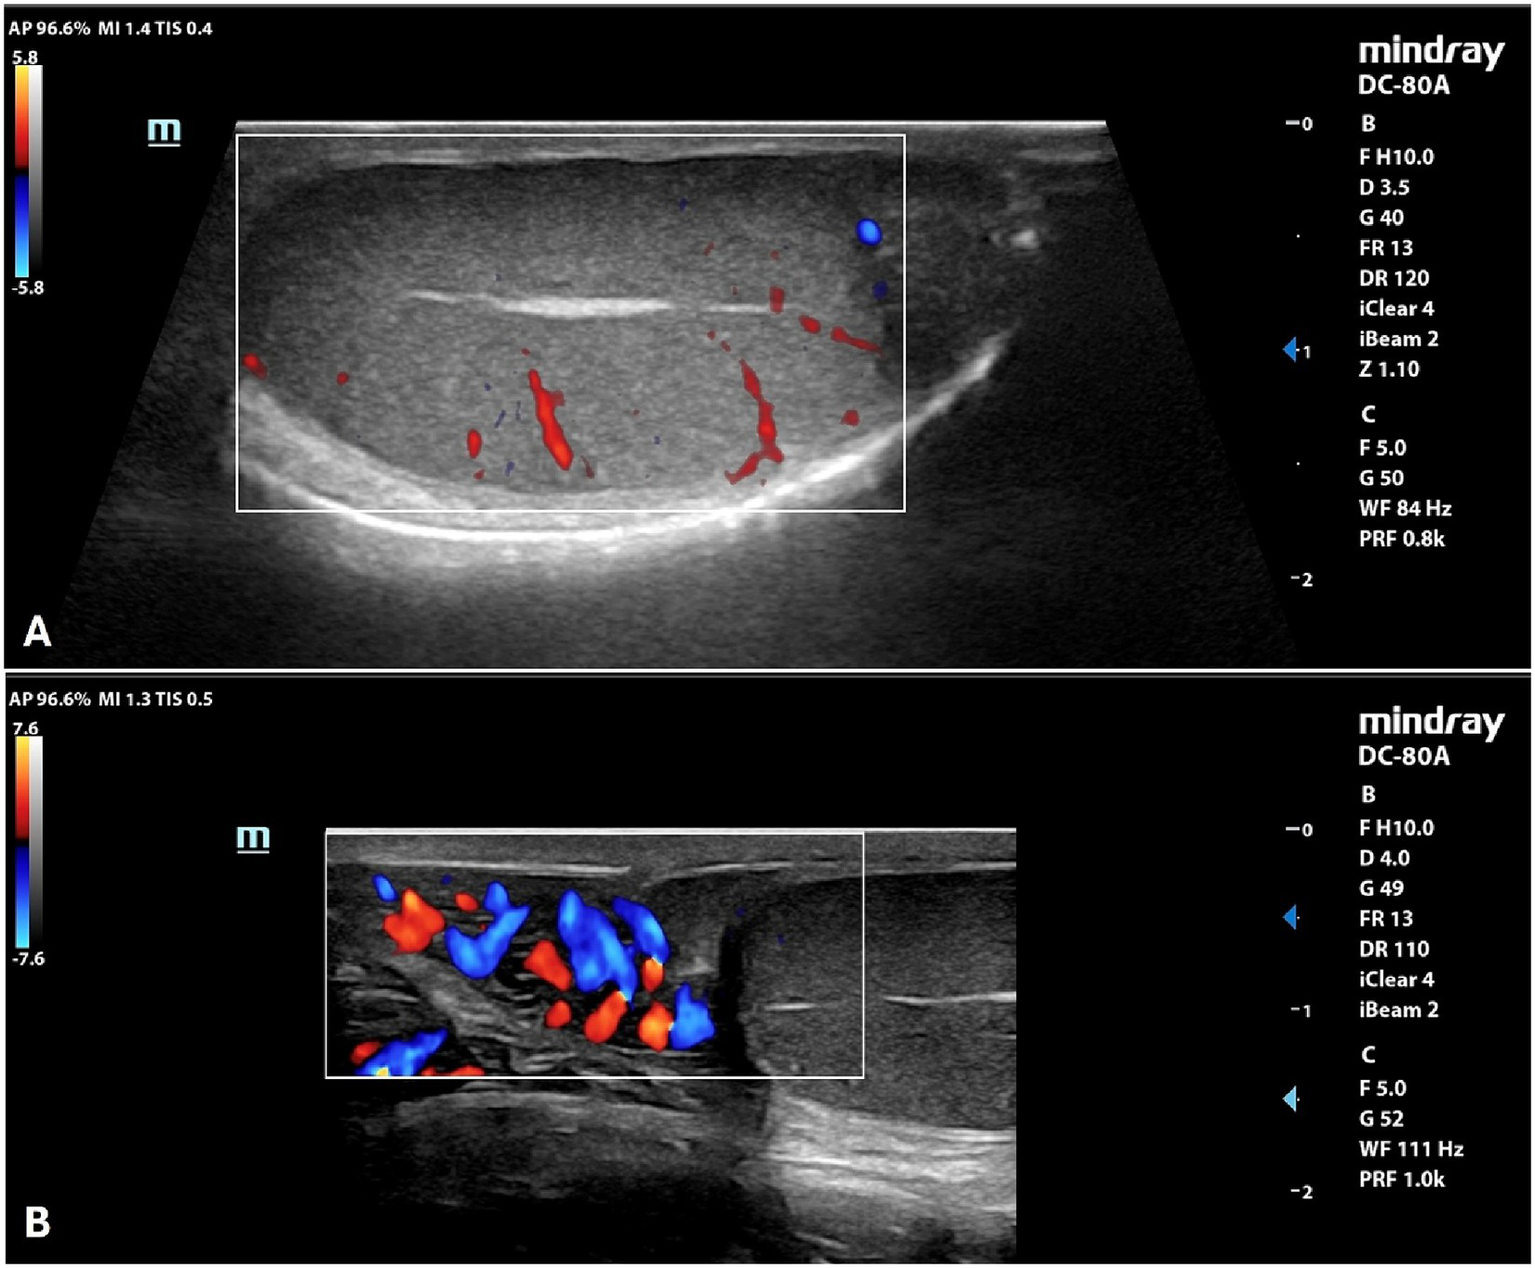

B-mode and Doppler ultrasound

By B-mode ultrasound, the testes and the prostate of all the dogs included were normal in size, margins, and parenchyma echotexture. The testes were ovoid in shape, with regular margins characterized by a thin and hyperechoic line (tunica albuginea). Testicular parenchyma presented medium echogenicity with a fine and homogeneous echotexture, interrupted by the presence of the mediastinum in the central part of the testis, which appeared as a hyperechoic line or spot, in the longitudinal and transverse scans, respectively. The prostate showed a rounded shape, with smooth margins and a homogeneous fine-coarse, medium-echoic texture. Color and power-Doppler examinations of testicles, prostate and spermatic cord showed the presence of widely distributed arterial and venous blood flows (Figure 1). Quantitative testicular and prostatic ultrasound evaluations showed a mean total testicular volume (TTV) of 16.62 ± 4.36 cm3 and a mean prostatic volume (PV) of 10.88 ± 4.18 cm3 (Table 2).

Figure 1

Color Doppler examination of the testicle (A) and spermatic cord (B) of a normal canine testicle.